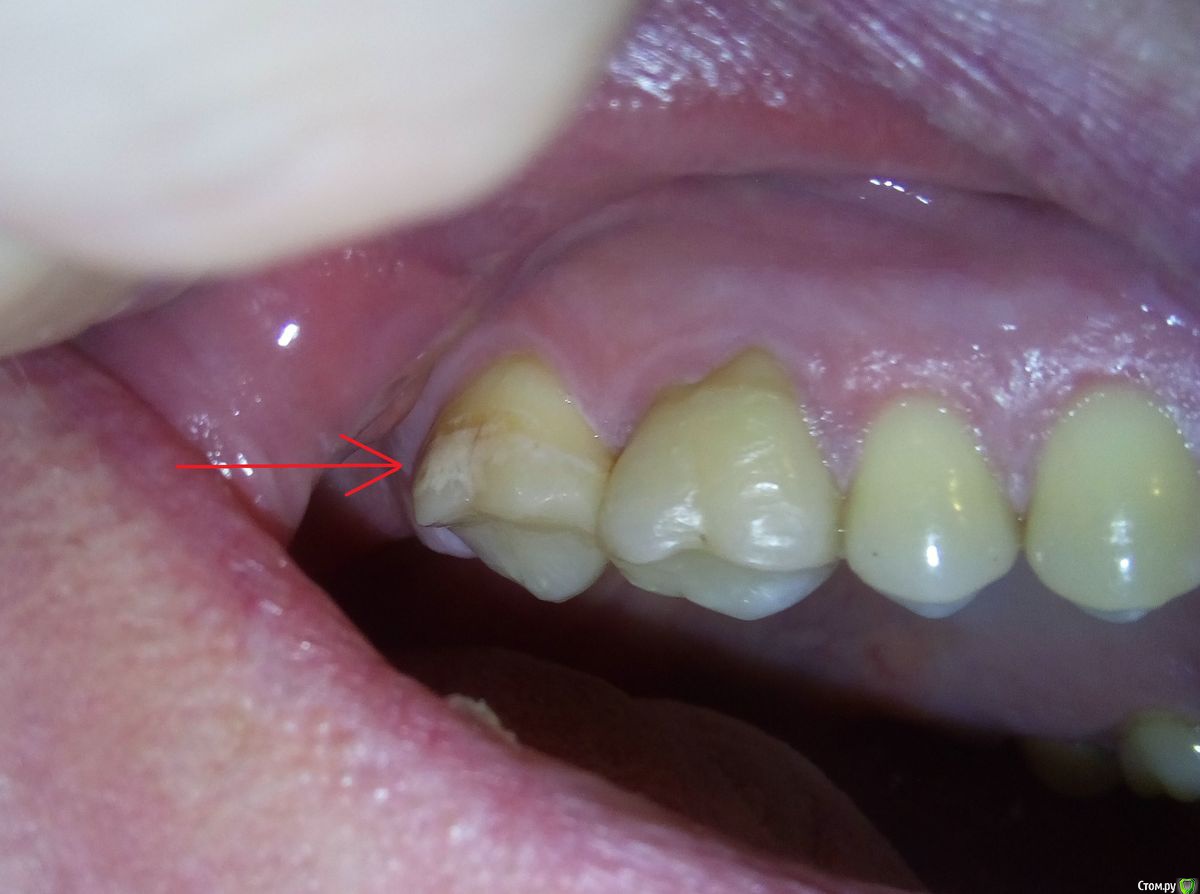

usilitel Опубликовано 17 ноября, 2018 Поделиться Опубликовано 17 ноября, 2018 (изменено) После замены пломбы в верхней 7-ке зуб окрасился и стал довольно сильно реагировать на холодное.Перед перепломбировкой 7-ки зуб иногда болел в области корней, после перепломбировки боли не прошли, плюс добавилась реакция на холодное. Вопросы: 1) Нормально ли, что зуб окрасился после перепломбировки?2) Может ли быть причина окраски в том, что зуб "отравлен" из-за токсичности пломбы в соседнем зубе? Снимок 1 ПОСЛЕ перепломбировки 7-ки: Снимок 2 ПОСЛЕ перепломбировки 7-ки: Рентгеновский снимок ДО перепломбировки 7-ки: Рентгеновский снимок ПОСЛЕ перепломбировки 7-ки - отсутствует. Моя версия (я не профессионал, так что сужу по собственным ощущениям):1,5 года назад при замене пломбы в соседней 6-ке пломбу скорее всего недосветили, и это сделало пломбу токсичной для зуба.1 год назад в 6-ке запломбировали каналы, но стало еще хуже (появилась невралгия, зуб реагирует при постукивании, зуд в области корней, болит глаз, стреляет в висок). При этом 6-ку удалять никто не хочет, т.к. на снимках всё более-менее нормально. Я думаю что из-за токсичности пломбы воспалились ткани вокруг 6-го зуба.Дальше это отравление в 6-ке перекинулось на 7-ку, и 7-ка тоже стала "отравленной". Из-за этого при замене пломбы 7-ка окрасилась и стала реагировать на холодное.Повторюсь - это моё непрофессиональное мнение, сужу по собственным ощущениям. Изменено 17 ноября, 2018 пользователем usilitel Ссылка на комментарий

red_butler Опубликовано 17 ноября, 2018 Поделиться Опубликовано 17 ноября, 2018 Ничего не окрасилось, это кариес в стадии пятна Ссылка на комментарий